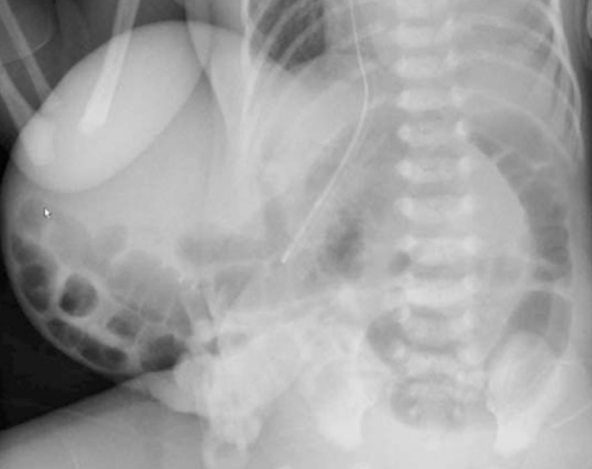

Babygramme

- Masse centrée sur la ligne médiane contenant du digestif

- Chercher d’autres malformations